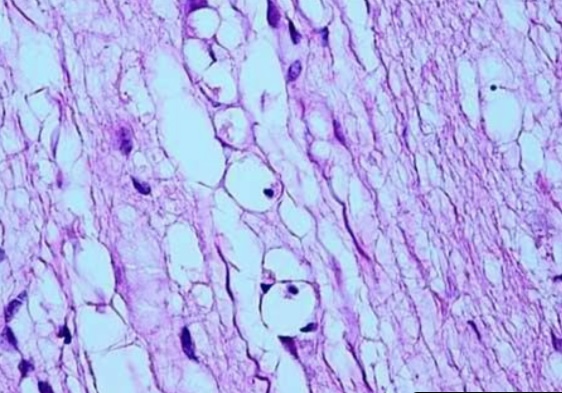

Fatty infiltration